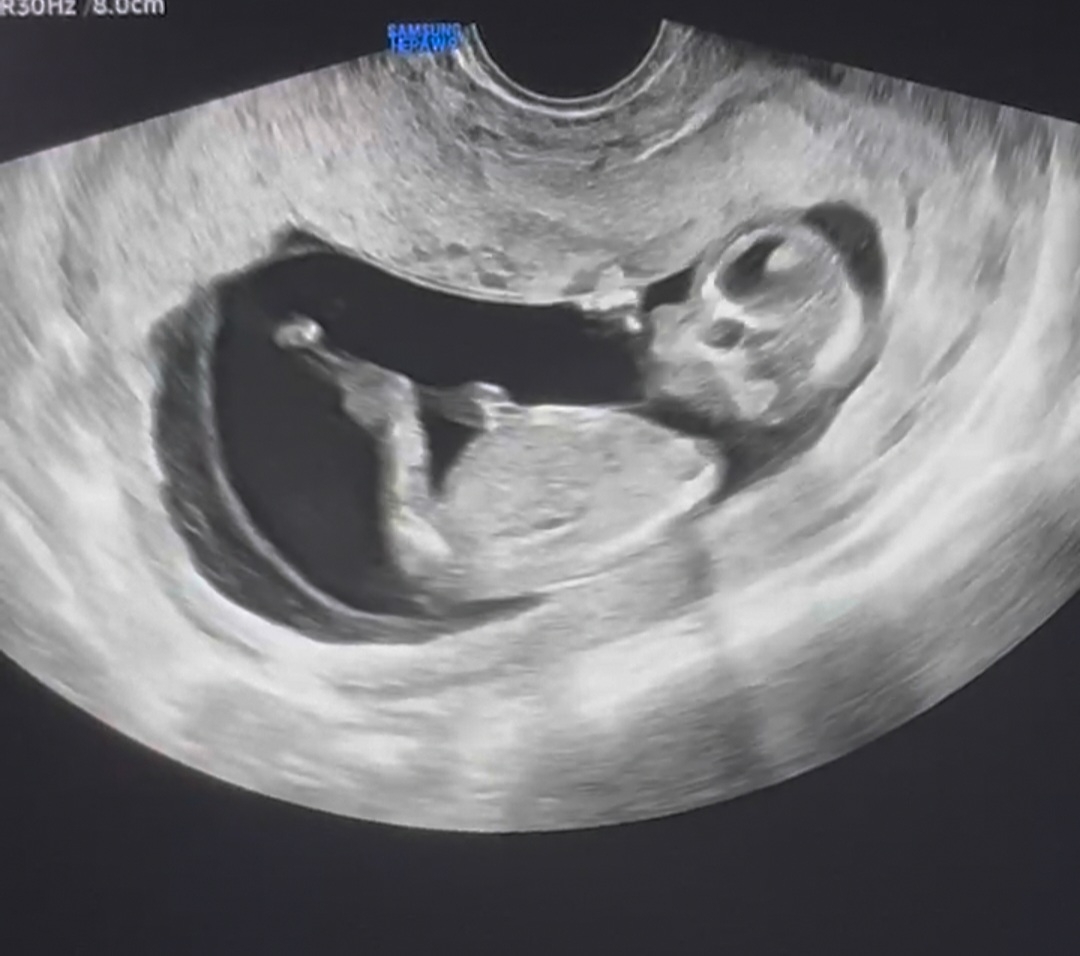

12주차 초음파 각도법 어떻게 알수있나요! 부탁드릴게요